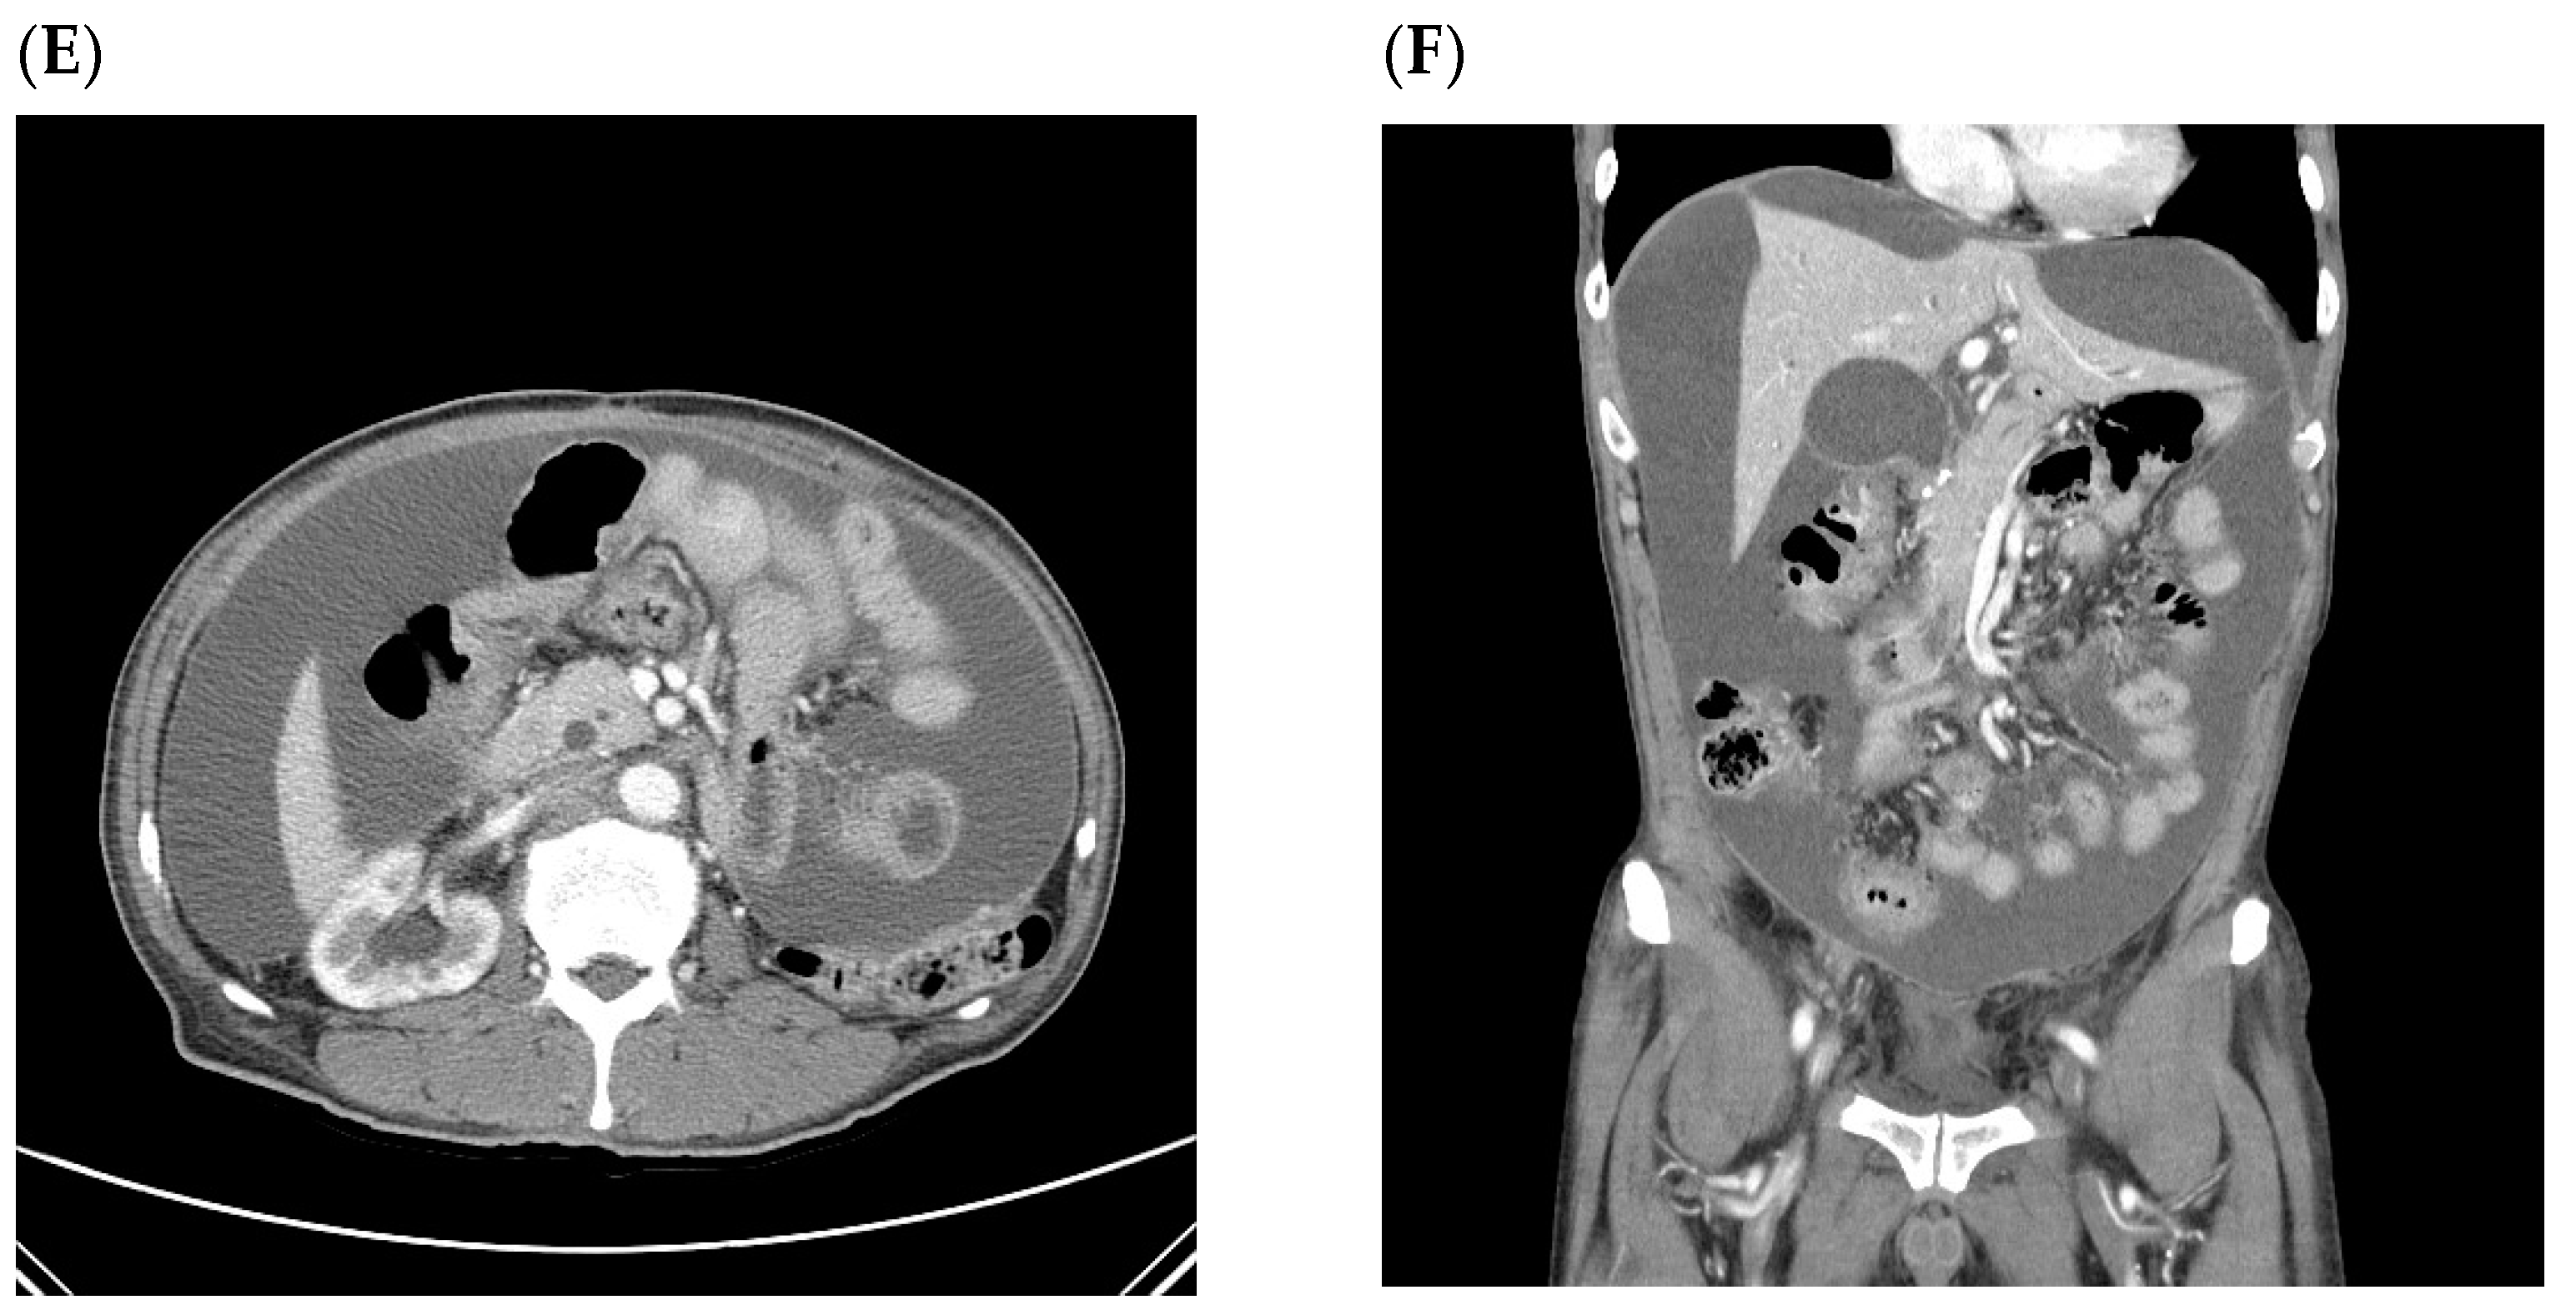

| Pt 1 | 65/M | PG | T3N3a | small pelvic cavity | Simultaneous with recurrence | T colon (increased ascites in the pelvic cavity) | 44.4 | 8.1 |

| Pt 2 | 53/F | TG | T4bN3b | small pelvic cavity | Simultaneous with recurrence | Peritoneum (increased ascites, peritoneal thickening, bowel obstruction, and Krukenberg tumors) | 18.2 | 13.2 |

| Pt 3 | 40/F | TG | T4aN3a | small pelvic cavity | Simultaneous with recurrence | Peritoneum (nodularity and increased ascites) | 73.2 | 70.3 |

| Pt 4 | 59/F | TG | T4aN3a | small pelvic cavity | Simultaneous with recurrence | Peritoneum (increased ascites and peritoneal thickening) | 25.2 | 21.7 |

| Pt 5 | 39/F | TG | T3N3b | small pelvic cavity | Simultaneous with recurrence | Peritoneum (Krukenberg tumors, nodularity, and increased ascites) | 12.1 | 9 |

| Pt 6 | 57/F | TG | T3N3a | small pelvic cavity | Simultaneous with recurrence | Peritoneum (bowel obstruction and increased ascites) | 9.8 | 4.4 |

| Pt 7 | 61/F | TG | T3N1 | small pelvic cavity | Simultaneous with recurrence | Peritoneum (increased ascites, T colon, and mesentery LNs) | 29.6 | 26 |

| Pt 8 | 68/F | PG | T4aN2 | small pelvic cavity | Simultaneous with recurrence | Peritoneum (increased ascites and peritoneal thickening) | 11.7 | 5.3 |

| A patient who first recurred with malignant ascites without other CT findings related to peritoneal seeding (later confirmed by cytology) (n = 1) | ||||||||

| Pt 9 | 49/F | TG | T3N3a | small pelvic cavity | ||||